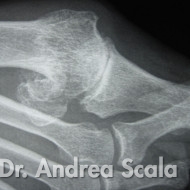

IMG 1 – La radiografia mostra un alluce rigido in fase iniziale.

IMG 2 – La radiografia mostra un alluce rigido più grave l’alluce ed il 1° metatarso sono quasi in contatto.